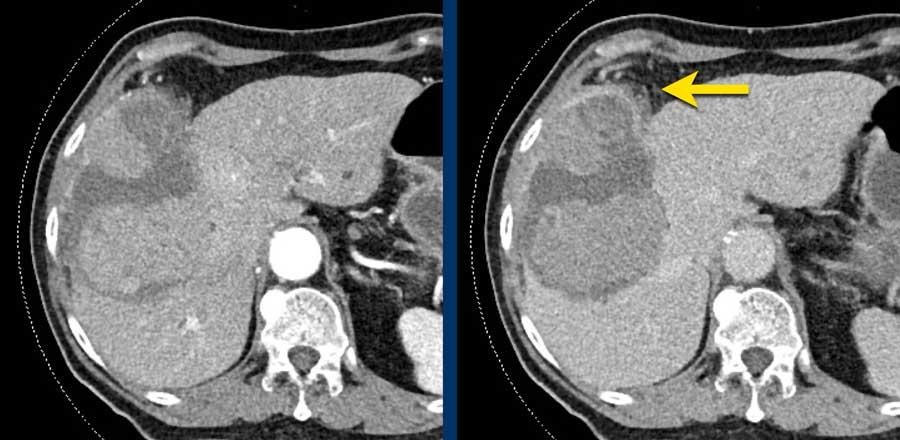

Đây là hình ảnh thì động mạch muộn của một bệnh nhân xơ gan.

Ghi nhận một tổn thương có tăng ngấm thuốc không dạng viền (mũi tên vàng).

Ở thì muộn, tổn thương có hiện tượng washout.

Đây là những đặc điểm điển hình của HCC.